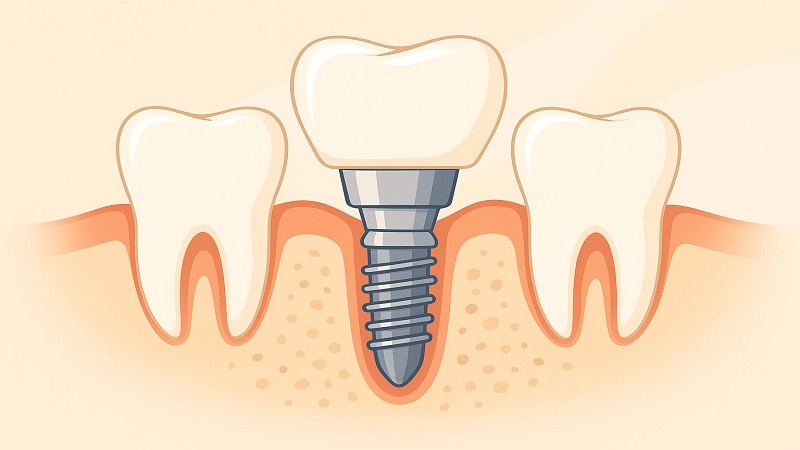

ایمپلنتهای دندانی از یک ماده زیست سازگار ساخته شدهاند که میتواند بدون مشکل مستقیماً با استخوان فک ادغام شود. تیتانیوم، فلزی با مقاومت بالا، رایجترین مادهای است که برای کاشت دندان آسیاب استفاده میشود.

برخی از دندانپزشکان از زیرکونیوم به عنوان جایگزین استفاده میکنند، زیرا رنگ سفید آن شباهت بیشتری به دندانهای طبیعی دارند. زیرکونیوم قیمت بیشتری نسبت به تیتانیوم دارد.

ایمپلنت دندانهای عقب، بهترین گزینه برای ترمیم دندان

ایمپلنت دندان های آسیاب بهترین گزینه برای ترمیم دندانهای از دست رفته هستند، زیرا عملکرد و ظاهر آنها درست مانند دندانهای طبیعی شماست. آنها یک دندان طبیعی و کاربردی را فراهم میکنند. با جایگزینی دندانهای آسیاب عقب از دست رفته، اطمینان حاصل میشود که دندانهای باقیمانده شما برای جبران شکاف به وجود آمده حرکت نمیکنند.